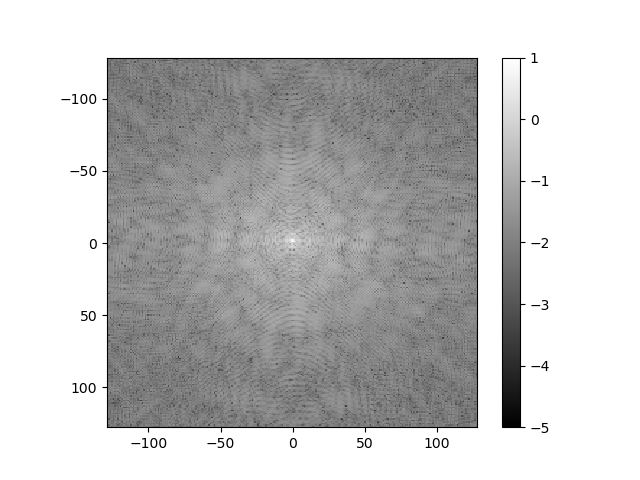

Consider how the image would change if the k-space data were multiplied by \sin^2(\cdot) or \cos^2(\cdot) of k_r or k_c. Below are several k-space representations that have been distorted in this way. In each case, assume that only the magnitude of the k-space data is changed. Match each k-space image with the corresponding reconstructed image, and enter your results from the corresponding pull-down list.